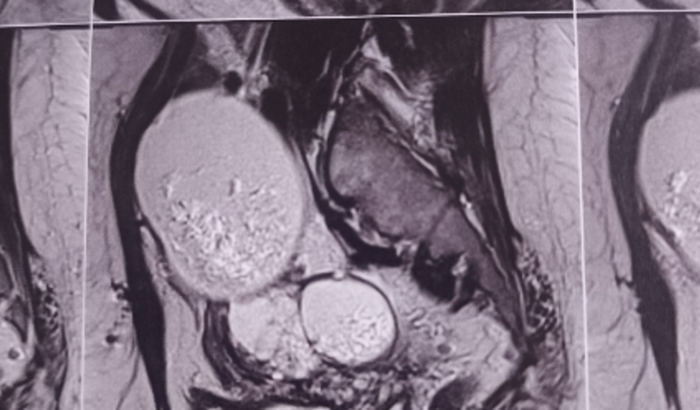

Me chamo Maria de Fátima, estou fazendo esta vaquinha para pagar a cirurgia de Histerectomia e Salpingooforectomia, cirurgia para retirada de dois tumores nos ovários,os quais causam muita dor e estão afetando e muito a minha saúde,sendo considerada benigna estou com bastante dificuldade para conseguir fazer com brevidade. Esse valor vai custear toda cirurgia,o pré e o pós operatório. Onde faço consultas periódicas com o oncologista e exames de rotina para cuidar a evolução do tumor. Preciso fazer a cirurgia com mas rapidez possível.